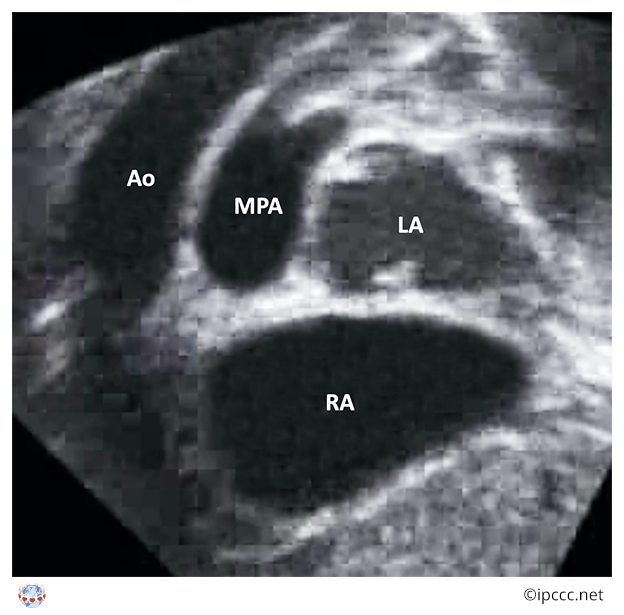

A congenital cardiovascular malformation in which the morphologically right atrium connects to the morphologically right ventricle, the morphologically left atrium connects to the morphologically left ventricle, the morphologically right ventricle connects to the aorta, the morphologically left ventricle connects to the pulmonary trunk, and a ventricular septal defect is not present.

Echocardiogram